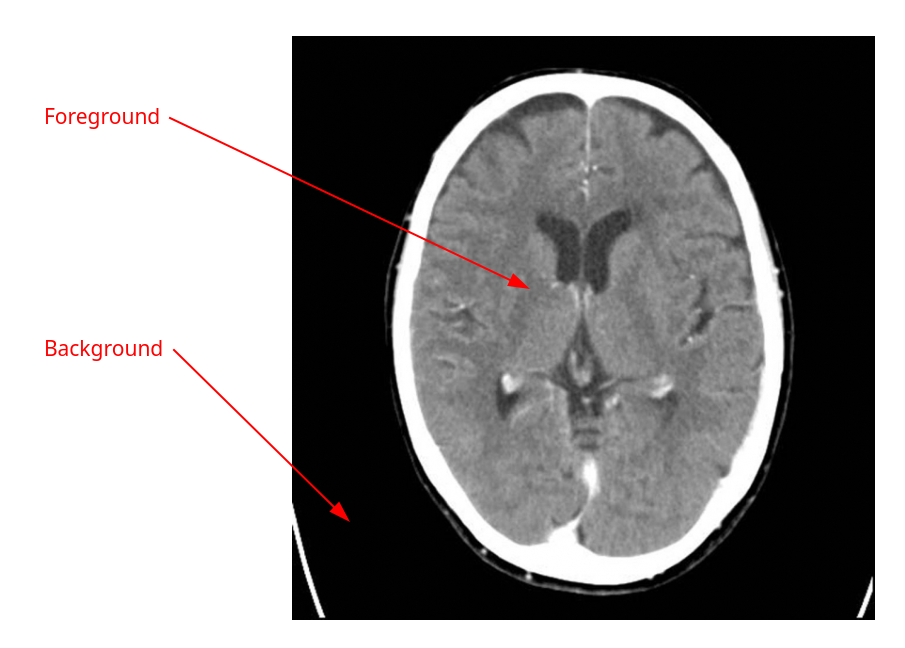

3. Image Segmentation via Min-Cut

Problem

We are given an image modeled as a graph where:

- = set of pixels

- = adjacency of neighboring pixels

Each pixel has:

- : cost of assigning to the foreground

- : cost of assigning to the background

Each edge has:

- : cost of cutting this edge (i.e., separating and )

Goal: Assign each pixel to foreground or background to minimize segmentation cost.

/Semester-2/Algorithms-and-Probability/Lecture-Notes/attachments/Pasted-image-20250523115701.png)